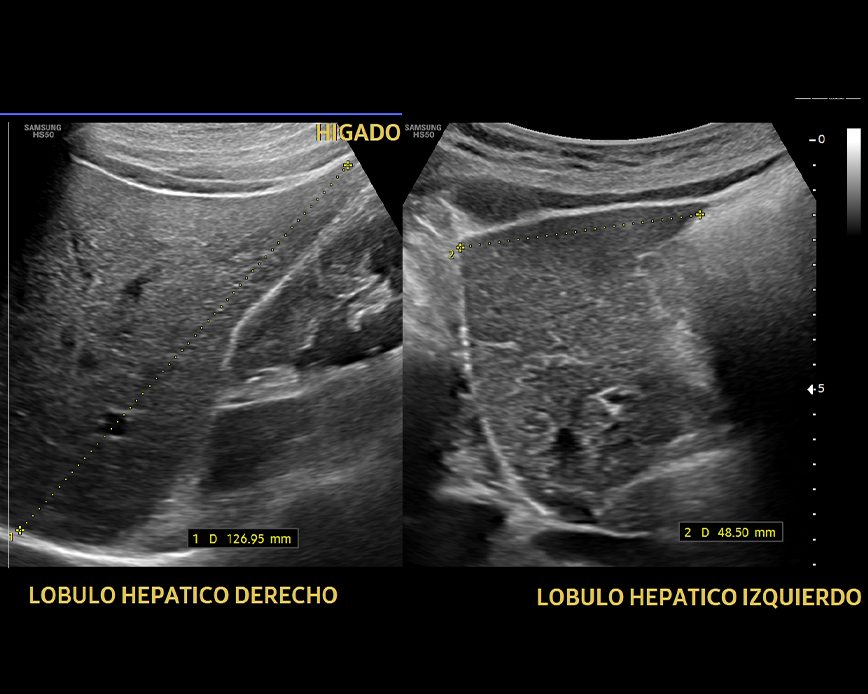

Ecografía Abdomen superior

- Diagnostico de enfermedades hepáticas